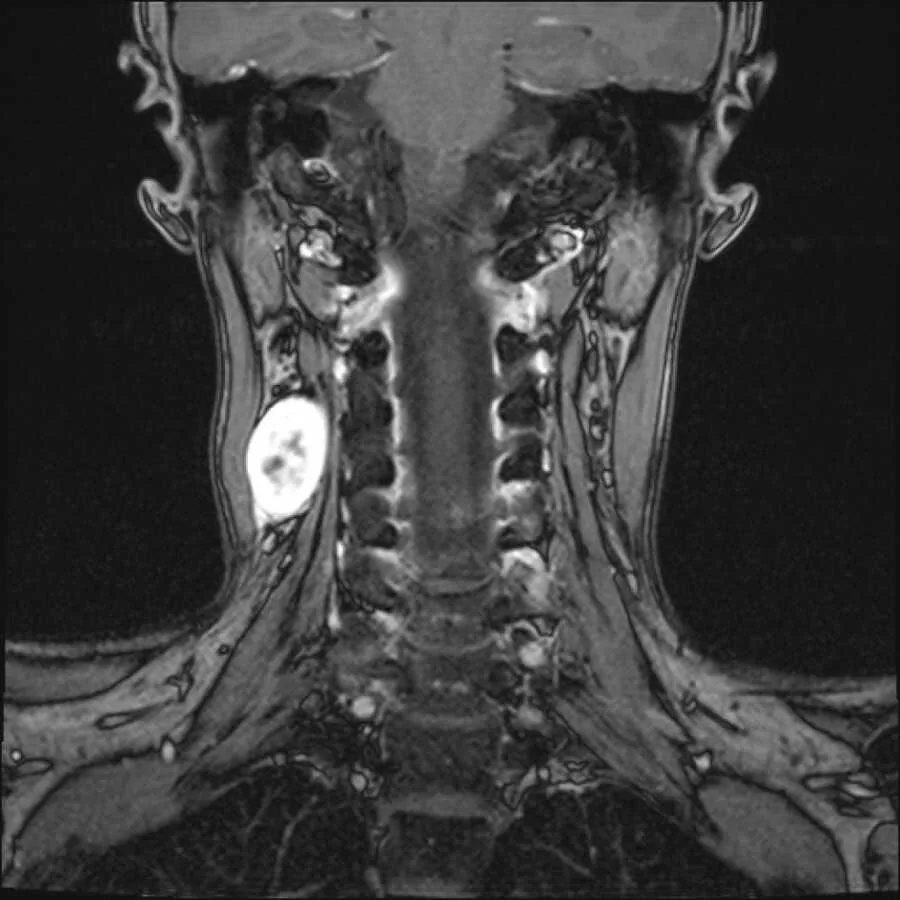

The diagnosis was a nerve sheath tumor, often benign, but tricky because it grows from the protective covering of nerves. That placement makes surgery hard; delay can press on nerves or the spinal cord. Since she had no significant symptoms yet, doctors suggested monitoring. So began years of MRIs, bills, and quiet fear. The tumor grew more than 20%, and although scans showed growth, they couldn’t say exactly which nerves were involved. Surgery became inevitable. Nerves could be irritated even if not cut; recovery could be slow or uncertain. She marked a date: December 29, 2021.